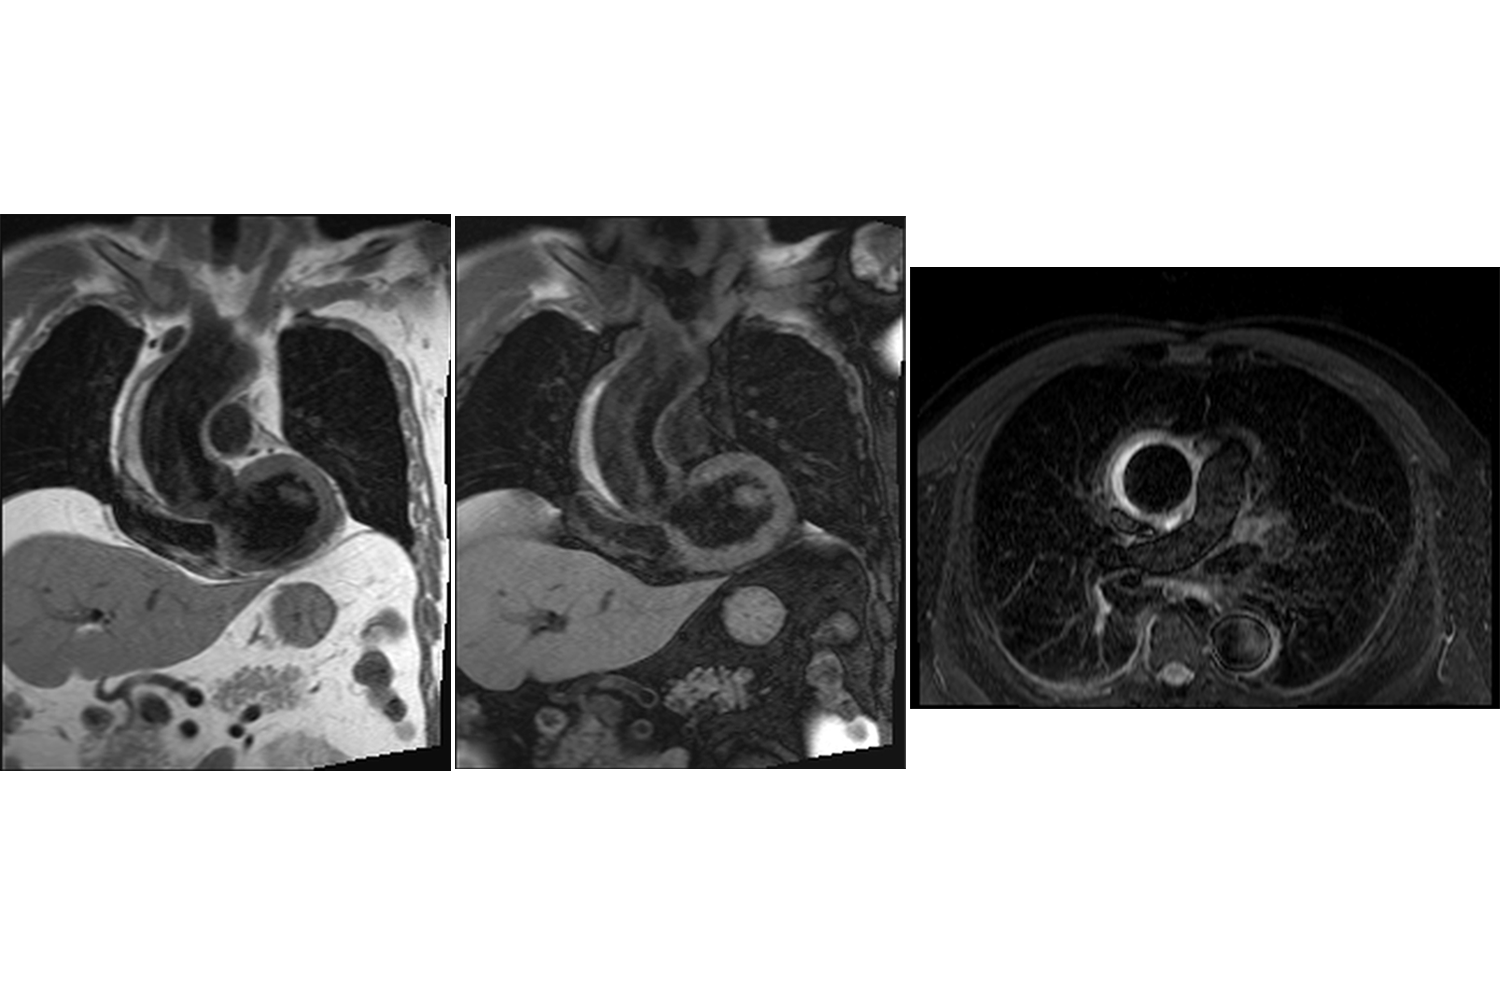

Image of the Week - 2 August 2023

Doctor Sriram Veeraraghavan

Doctor Bharath Raj Kidambi

Doctor Narendhiran Pandurangan